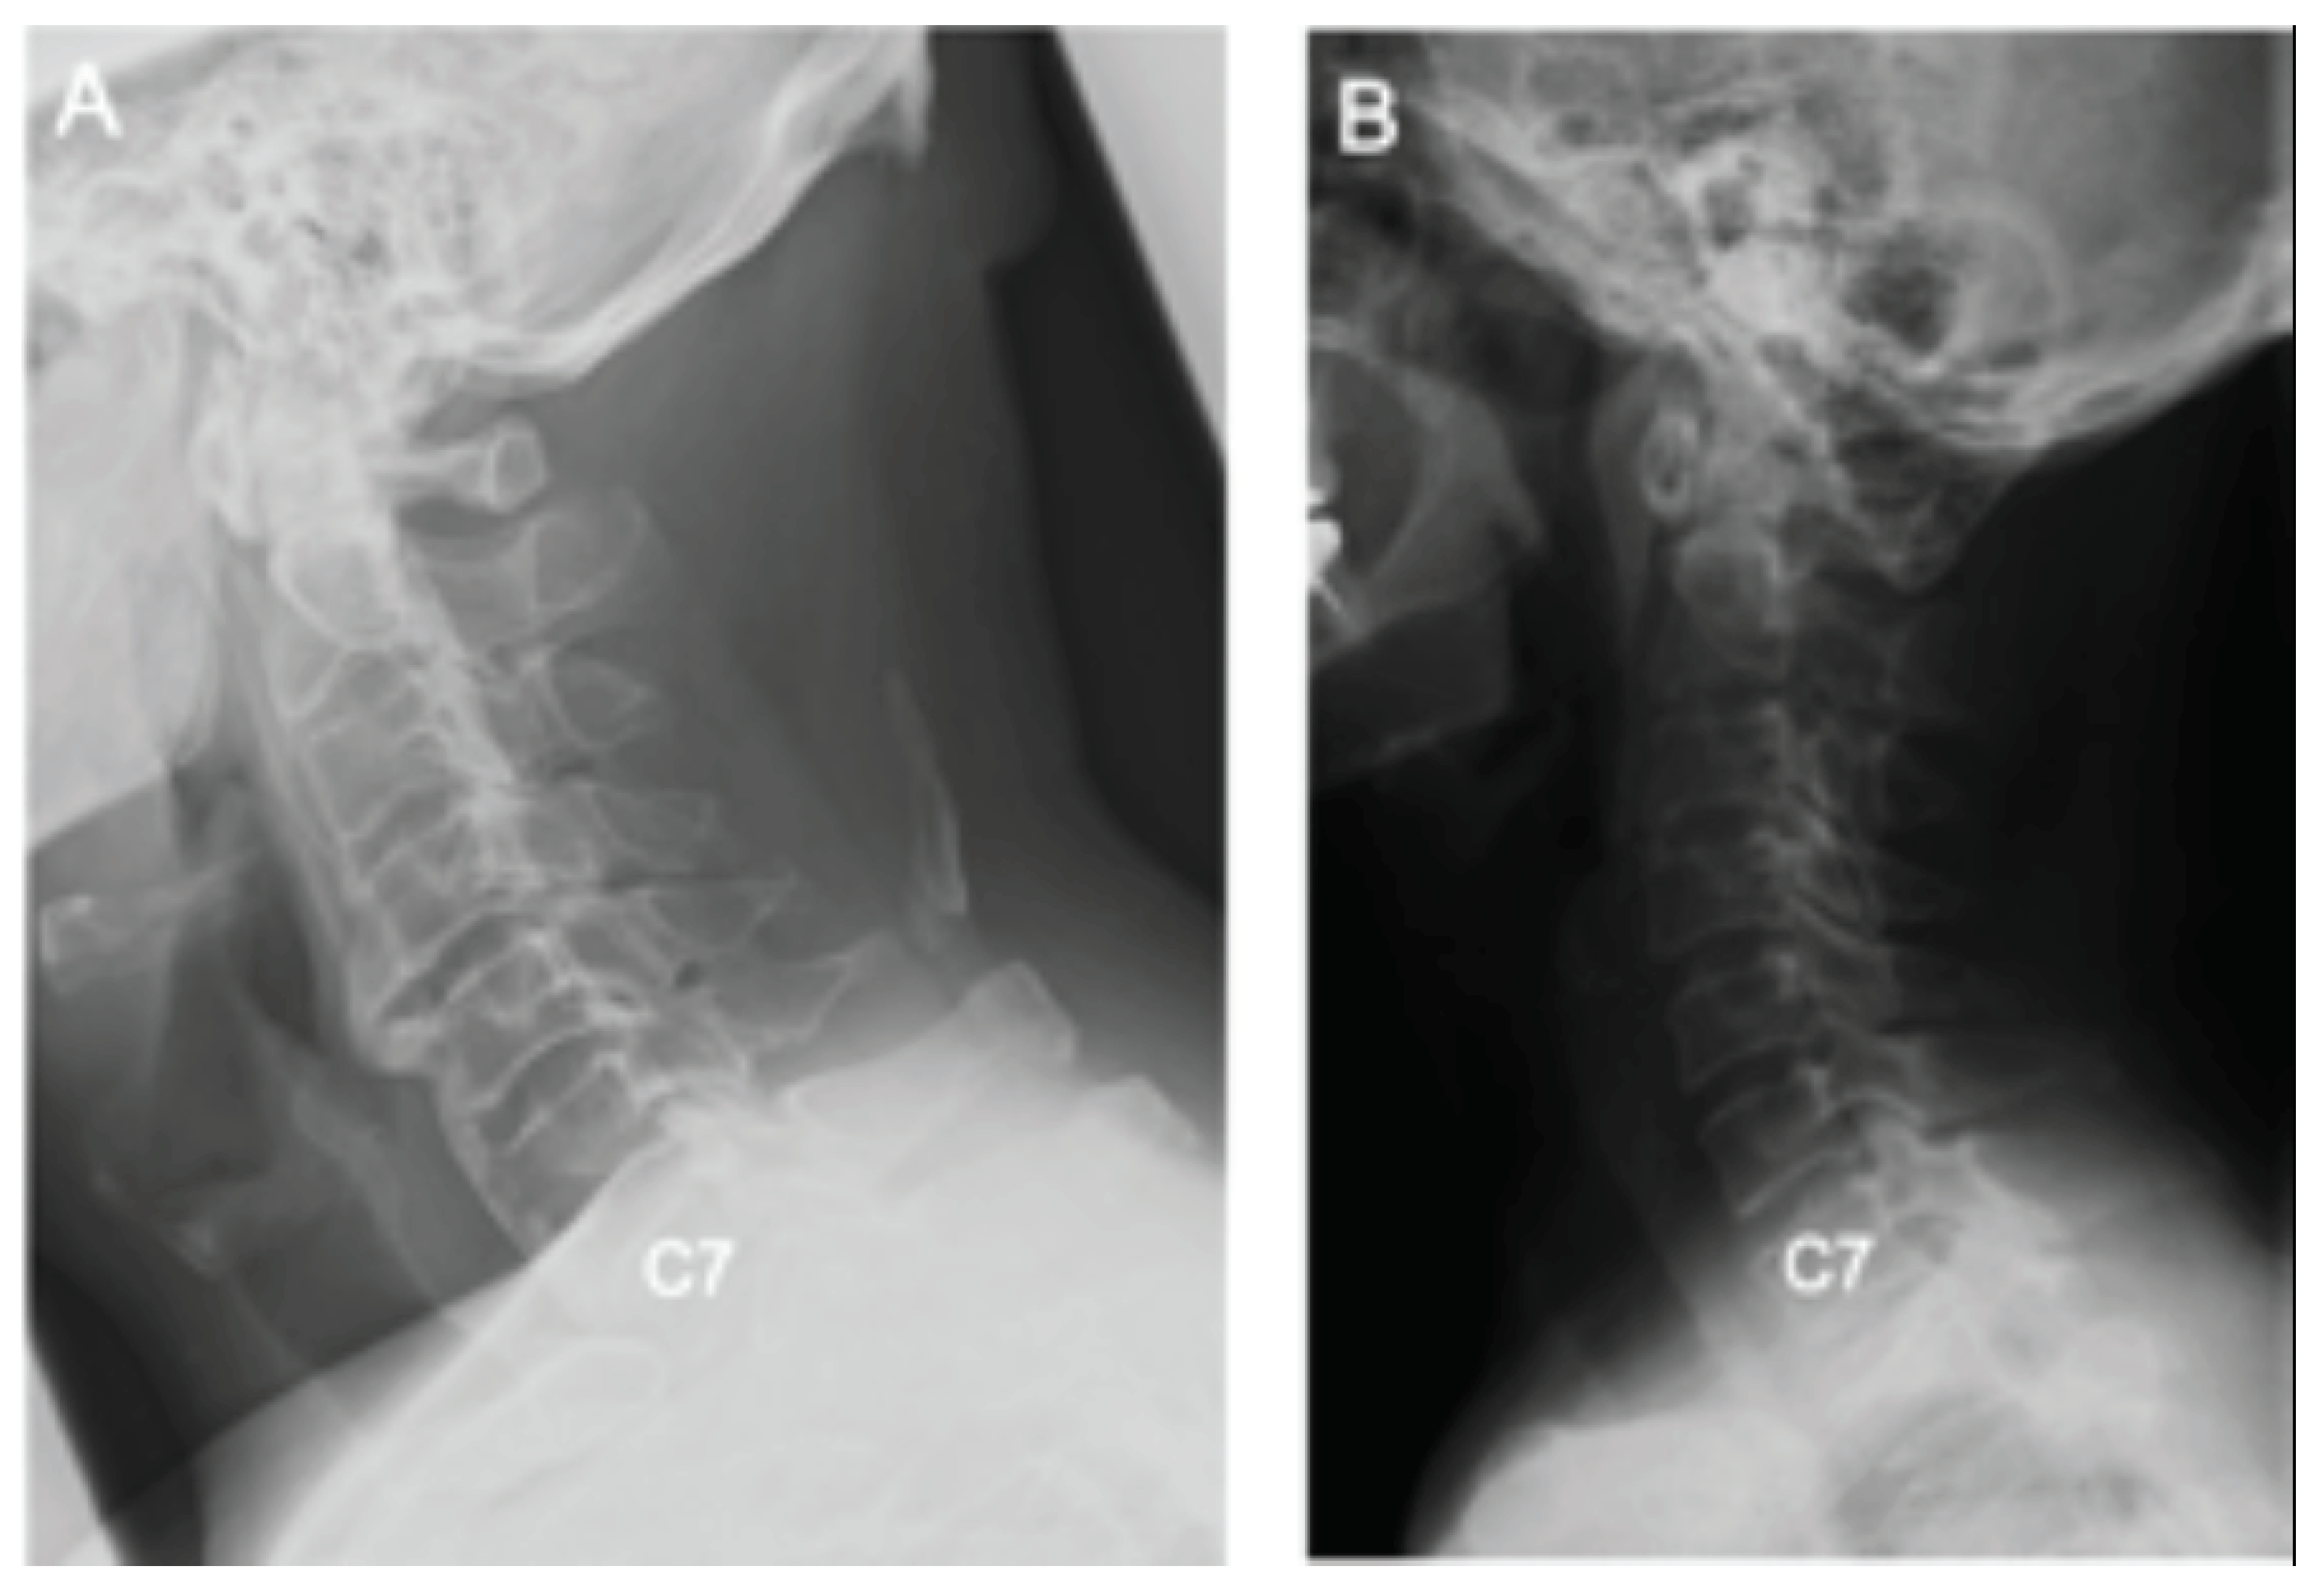

Differences in Demographic and Radiographic Characteristics between Patients with Visible and Invisible T1 Slopes on Lateral Cervical Radiographic Images

2.2. Radiological Assessment